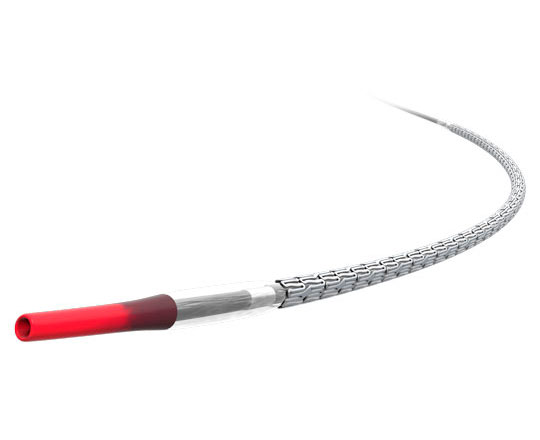

True Flow (Bard, EEUU) es un balón de valvuloplastia que permite el flujo a su través mientras está inflado. Su recubrimiento exterior está compuesto por un tejido de fibras que evita el deslizamiento del balón al abrirse sobre los velos valvulares, por lo que no se necesita estimular el corazón con marcapasos. Este tejido esta formado por poliuretano de alto peso molecular, poliéster y fibras de aramida (componente estructural del Kevlar) que posee una baja distensibilidad y alta resistencia a la rotura. El interior del balón tiene 8 globos de pequeño diámetro en el perímetro del balón principal, y deja un espacio entre ellos por donde fluye la sangre. El dispositivo mide 3,5 cm de largo y está disponible en seis tamaños, con diámetros que van de los 18 a los 26 mm. Los más pequeños son compatibles con un introductor de 11 French y el más grande con introductor de 16 French.